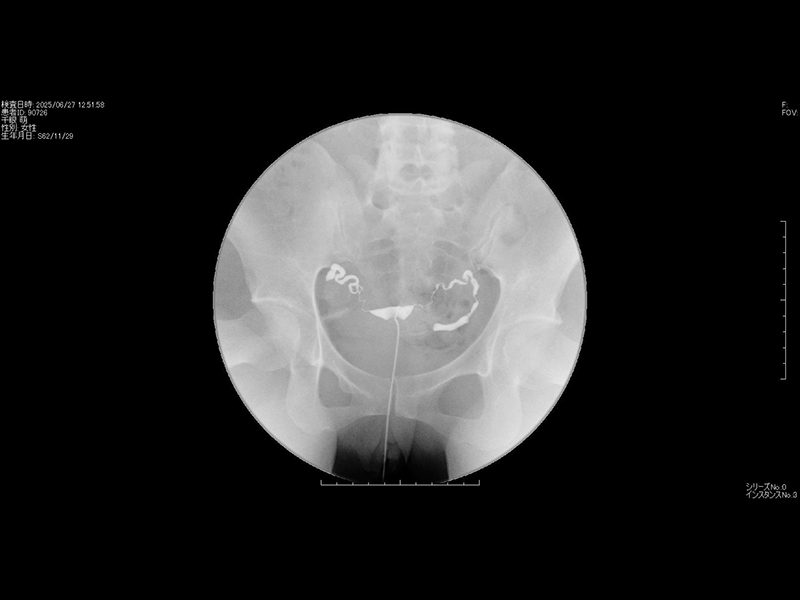

3卵管造影検査

卵管造影検査は子宮の入り口から造影剤を注入し、その造影剤が子宮から卵管へと流れ、最終的に腹腔内に広がる様子をX線撮影(レントゲン)で確認する検査です。不妊の原因の約30%は卵管因子と言われており、この検査は卵管性の不妊の有無を診断するために不可欠です。